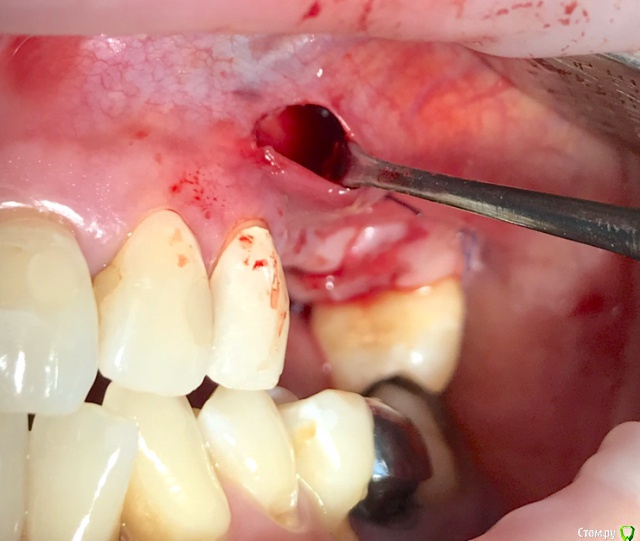

колесников Опубликовано 20 августа, 2019 Автор Поделиться Опубликовано 20 августа, 2019 Очередной случай тоннельной пластики альвеолярного гребня. Был небольшой бонус в виде лунки 26го зуба с дефектом вестибулярной стенки и оас. Лунка консервирована и закрыта «быстрым Ноймайером»,24,25 тоннельный графтинг. Графт тот же,шурос кортикальный без добавок.Контроль и имплантация через 4 мес,через неделю фиксация временной реставрации. Через 2-3 проверим на состоятельность. 4 Ссылка на комментарий